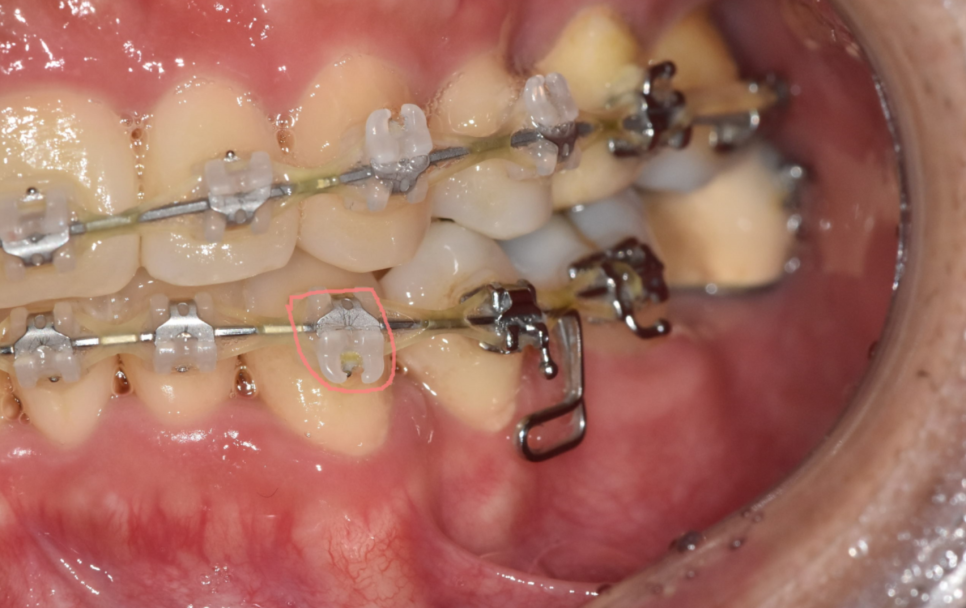

단, 브라켓 주변 또는 아래 쪽에 충치가 생기거나

큰 충치로 인해 인레이 등이 필요하거나

보철 치료가 필요한 경우

진행하고 있는 충치 등등

이런 경우는 브라켓을 잠시 제거 하고

충치 치료를 해야할 수 있습니다.

250116 교정 장치 하단에 생긴 충치는 장치 제거가 필요할 수 있습니다.

교정 기간동안 악화될 수 있기 때문이죠.